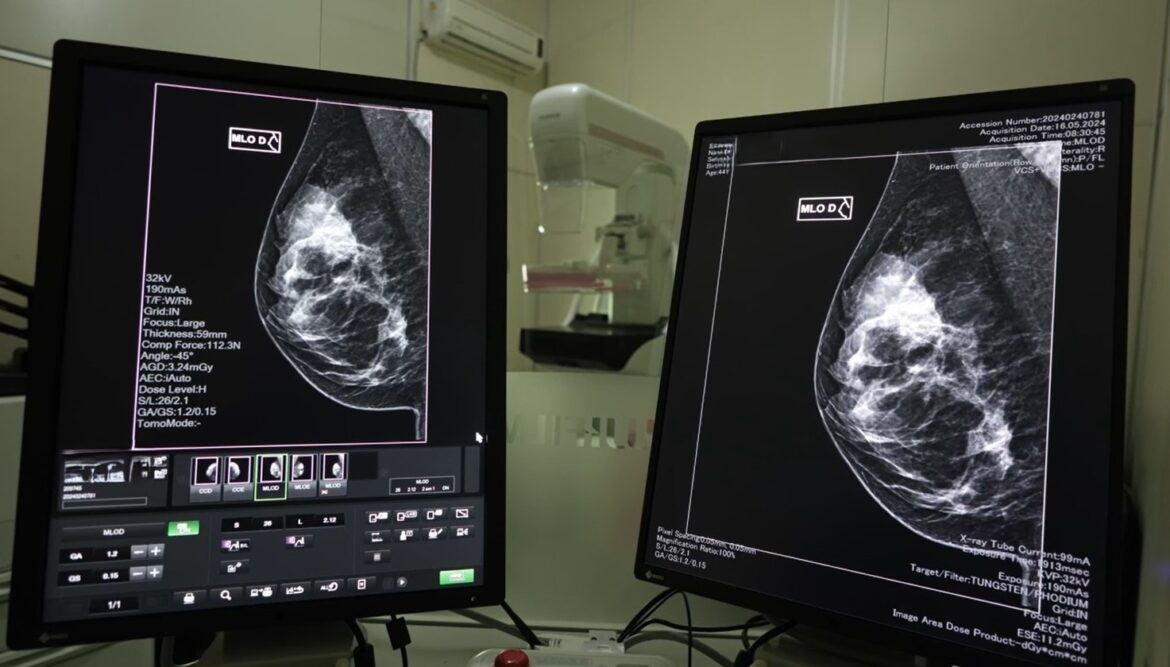

Em 2024, mais de 2,5 mil mulheres receberam o diagnóstico de câncer de mama e 167,2 mil mamografias foram realizadas pelo Sistema Único de Saúde (SUS). Além disso, as unidades habilitadas em oncologia realizaram 613 cirurgias desta neoplasia no ano passado.

A detecção precoce do câncer de mama é fundamental para aumentar as chances de tratamentos menos invasivos e com maiores taxas de sucesso. As mamografias são realizadas pelo SUS, via Atenção Primária à Saúde, com prestadores dos municípios e Consórcios de Saúde. Hospitais de gestão estadual que prestam serviços de saúde da mulher e possuem mamógrafos também realizam os exames.